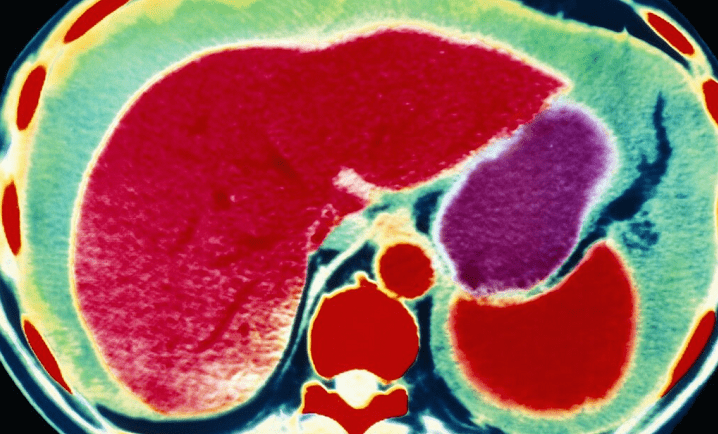

肝脏|医生提醒:这3种蔬菜被列入肝病“黑名单”,有肝病的人要少吃

肝脏是人体代谢和解毒的主要器官 , 十分重要 , 但是因为平时人们对肝脏疏于保养 , 让肝病成为一种高发病 。 如果在患上慢性肝病之后还不引起重视 , 那么就极有可能转化成肝癌 , 对生命造成很大的威胁 。